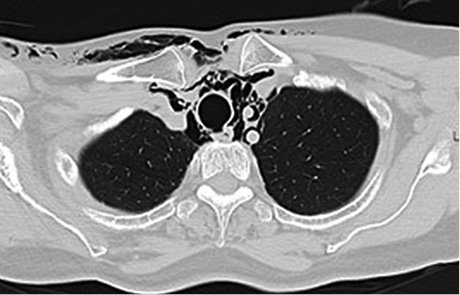

A cranial and thoracic computed tomography (CT) showed diffuse soft tissues emphysema from the thoracic region to the neck and face (Figure 2), and mediastinal emphysema in all compartments (Figure 3), and interruption of tracheal continuity 4 cm cranial from the bifurcation (Figure 4).

Figure 4. Interruption of tracheal continuity